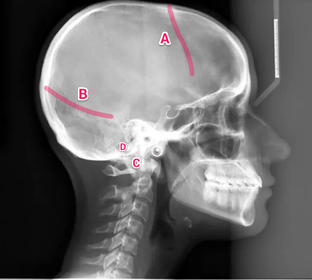

Anatomy practical midyear flashcard revision

anatomy

x-ray